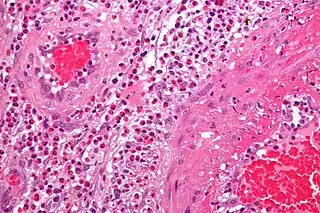

La vasculitis engloba todos aquellos síndromes y enfermedades que cursan con inflamación de los vasos sanguíneos (vénulas, capilares y arteriolas de mediano y gran calibre) tanto de órganos específicos como generalizadas.[1][2]

Patogenia

Los dos mecanismos más conocidos por los que se produce una vasculitis son:

- Inflamación de origen inmunitario

- Mediadas por el sistema del complemento

- Mediadas por anticuerpos (síndrome de Goodpasture)

- Mediadas por inmunidad celular

- Invasión directa de las paredes vasculares por agentes patógenos